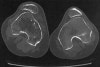

영상 검사

Lateral view는 슬관절 30도 굴곡 상태에서 patellar alta, genus valgum, hypoplasia of lateral femoral condyle가 보입니다.

Axial view는 슬관절 45도 굴곡 상태의 merchant view로 PF joint에서 슬개골의 모양 및 위치를 확인합니다.

MRI에서는 슬개골 관절 연골의 상태를 평가, 관절내 유리체 및 기타 동반질환을 확인합니다.